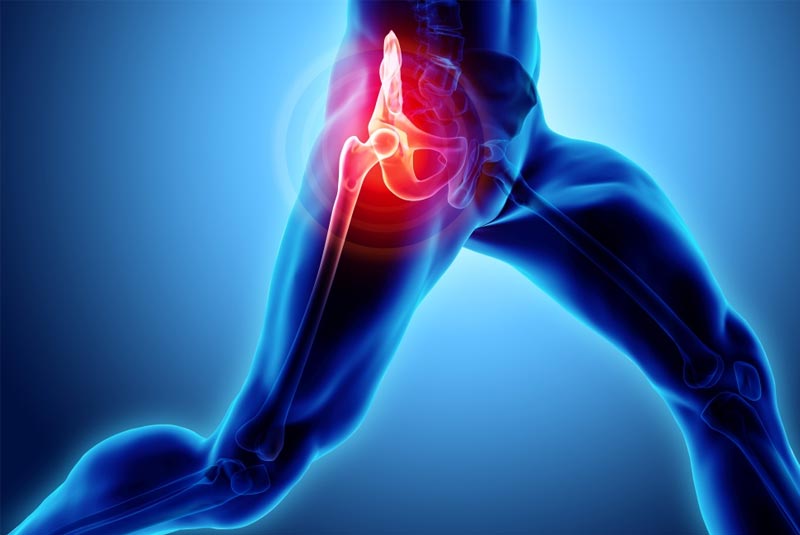

Έχει 5ετή μετεκπαίδευση και εργασία στο Ηνωμένο Βασίλειο ως ειδικός Ορθοπαιδικός Χειρουργός. Έχει εργαστεί στα Ορθοπαιδικά Τμήματα των Νοσοκομείων Southampton University Hospitals NHS Trust, Leeds Teaching Hospitals NHS Trust και στο Northampton General Hospital NHS Trust, με υποεξειδίκευση στη Χειρουργική Ώμου, Γόνατος, Ισχίου, Ποδοκνημικής & Άκρου Ποδός, Ώμου & Αγκώνος και Γενικού Τραύματος Ενηλίκων και Παίδων.

Κατά τη διάρκεια της εργασίας του στο Ηνωμένο Βασίλειο εκπαιδεύτηκε σε σύγχρονες τεχνικές Αρθροσκοπικής Χειρουργικής και Επανορθωτικής Χειρουργικής Ισχίου, Γόνατος και Ώμου. Επιπλέον έχει δώσει πολυάριθμες διαλέξεις και έχει εκπαιδεύσει νεότερους Ορθοπαιδικούς και φοιτητές Ιατρικής. Αξιοσημείωτο και πλούσιο είναι το επιστημονικό του έργο με συμμετοχή σε δεκάδες συνέδρια και σεμινάρια στην Ελλάδα και στο εξωτερικό και έχει πληθώρα προφορικών ανακοινώσεων και δημοσιεύσεων.

Παθήσεις & Θεραπείες